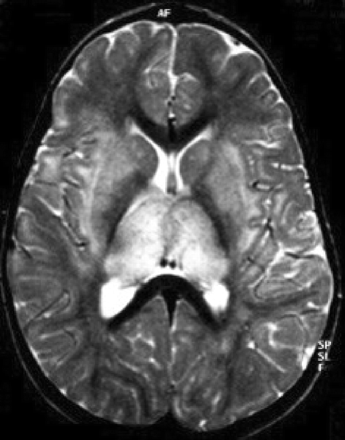

提出了四种模式的大脑参与描述ADEM的磁共振成像结果21:1)ADEM小病变(少于5毫米;图1);2)ADEM大支流,块状病变,簇状或频繁广泛perilesional水肿和质量效应(图2);3)ADEM附加对称bithalamic参与(图3);和4)急性出血性脑脊髓炎(咳咳),当一些出血的证据可以确定大脱髓鞘病变(图4)。核磁共振成像模式似乎并不与任何特定的结果或残疾,作为大型儿童群体中观察到,21因为大多数病变往往解决后续成像研究。21日,32然而,这种分类可能是有用的在考虑的鉴别诊断ADEM和可能有助于识别那些孩子来说,初始ADEM-phenotype真的是第一个女士的表现。

图1所示。急性播散性脑脊髓炎与小病灶。(一)轴向t2加权MRI显示双边、不加边hyperintense病变在中央,室旁,juxtacortical白质,(B)包括花托和内部胶囊,一个17个月大的男孩,麻疹疫苗接种后2周。